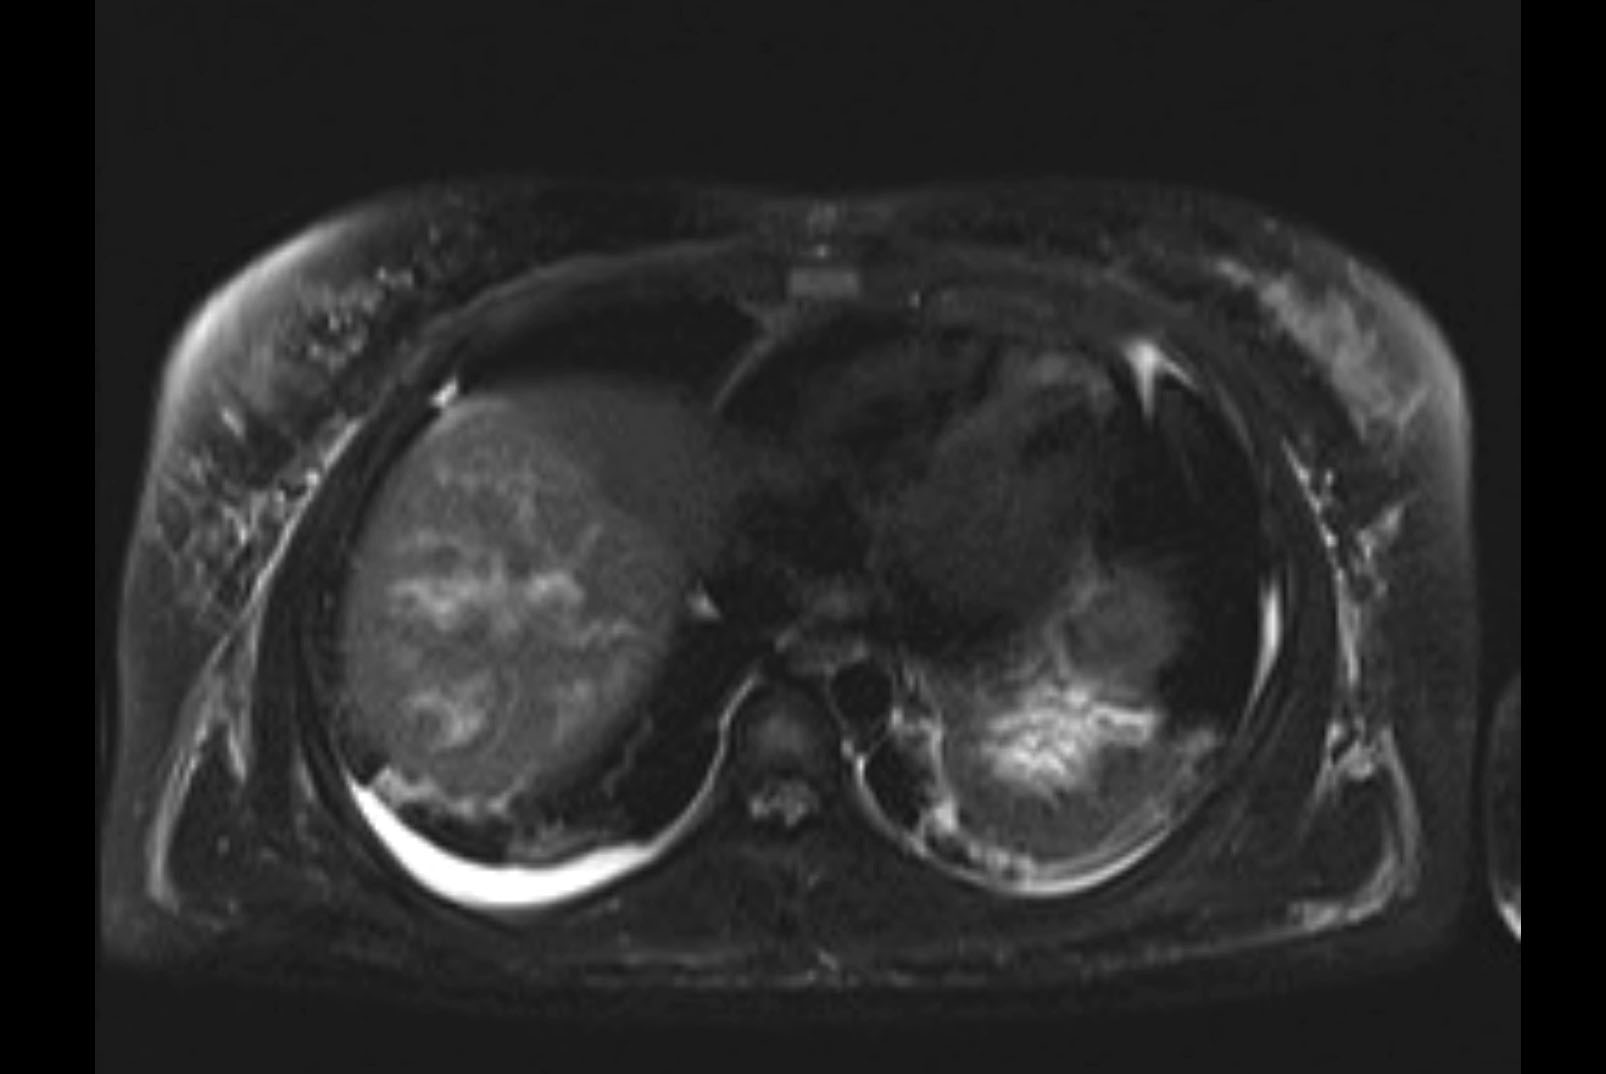

Imaging Analysis

Look through the patient's CT scan to identify any areas of concern for the necessary procedure.

MRI T1

MRI T2

Based on initial findings, which issue(s) would you be most concerned about?